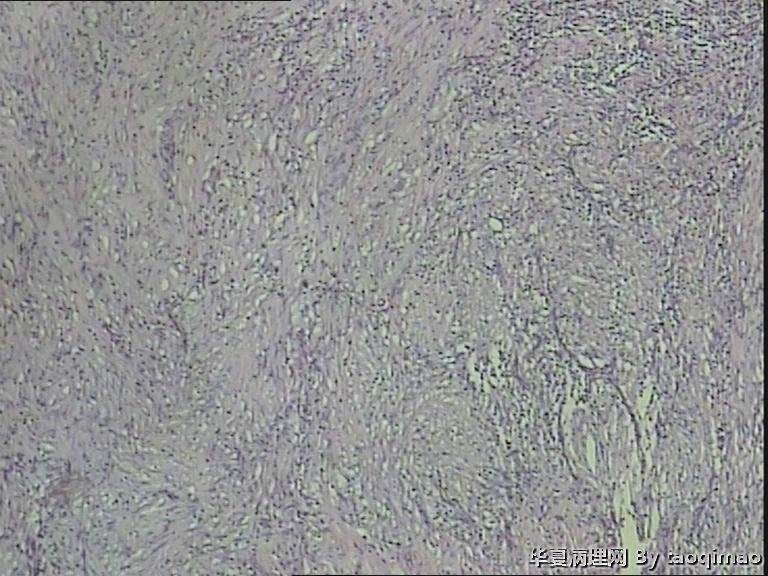

胃溃疡?

• 胃溃疡?图1

补取的组织

79岁女,胃溃疡,切除胃大部分,与脾有粘连,胃小弯侧可见一溃疡3x2.5x2cm,并且局部胃粘膜增厚,呈皮革胃样外观,切面灰白似粘液样。

胃低分化腺癌

令人困惑的切片!

肉眼既是巨大溃疡又是皮革胃,建议最好再取材,因为牵涉到后期治疗问题。

胃溃疡,黏液变,没看到明确的上皮样细胞

巨大溃疡临床诊断,可是看了间质很浆糊,希望老师们给指点些